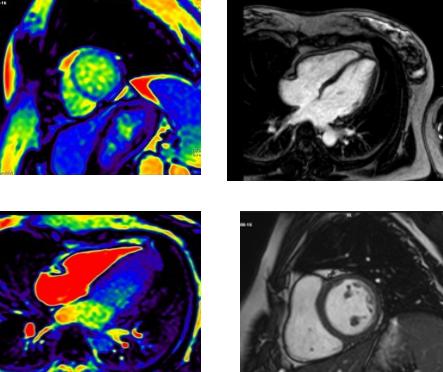

---延安大學(xué)咸陽醫(yī)院心血管內(nèi)科五病區(qū)與醫(yī)學(xué)影像科合作通過心臟MRI診斷心肌致密化不全一例。

新年伊始,心五科接診了這樣一名年輕女性患者。患者受涼1周后出現(xiàn)心慌、氣短不適,既往無危險(xiǎn)因素及心臟病史,入院后查動(dòng)態(tài)心電圖提示:頻發(fā)性室性早搏伴頻發(fā)短陣室性心動(dòng)過速,但患者心肌酶譜及心臟彩超均未經(jīng)明顯異常?;颊呔烤故鞘裁丛?qū)е麓祟悙盒孕穆墒СD??是冠心?。啃募〔??心肌炎?還是遺傳性心臟???在心五科主任李陽副教授、馮韓章責(zé)任總醫(yī)師及科室醫(yī)生的分析討論后,最終決定于2021年1月21日為患者進(jìn)行心臟磁共振檢查。在醫(yī)學(xué)影像科張利安責(zé)任總醫(yī)師、蔡雷主治醫(yī)師認(rèn)真讀片,院長助理兼醫(yī)學(xué)影像科主任劉連鋒教授最終確認(rèn)后,考慮心肌致密化不全??墒切募≈旅芑蝗质鞘裁礃拥囊环N疾病呢?

心肌致密化不全(海綿心肌病)是一種罕見的特殊類型的心肌病,屬于先天性、遺傳性心肌病,它表現(xiàn)為以心室內(nèi)異常粗大的肌小梁和交錯(cuò)的深隱窩為特征的一種與基因相關(guān)的遺傳性心肌病。心臟是由非常密集的肌肉細(xì)胞組成的,如果胎兒或后天疾病導(dǎo)致心肌細(xì)胞空間增大,即心臟沒有致密的肌肉結(jié)構(gòu),導(dǎo)致心肌致密化不完全,收縮力下降,心功能或心率改變,部分患者后果嚴(yán)重。一般主要是累及心臟的左心室,臨床表現(xiàn)多樣,從無癥狀到進(jìn)行性心功能惡化,充血性心力衰竭,心律失常,甚至猝死。

心肌致密化不全過去主要靠超聲心動(dòng)圖診斷,但由于分辨率問題,部分患者敏感性較低,有時(shí)需要經(jīng)食道UCG或心肌聲學(xué)造影,心臟MRI對NVM診斷敏感性可達(dá)86%,特異性達(dá)99%。經(jīng)過明確診斷,可提高患者對疾病的重視,提高醫(yī)生對患者疾病的認(rèn)識,為患者提供更優(yōu)化的治療措施及預(yù)后判斷。